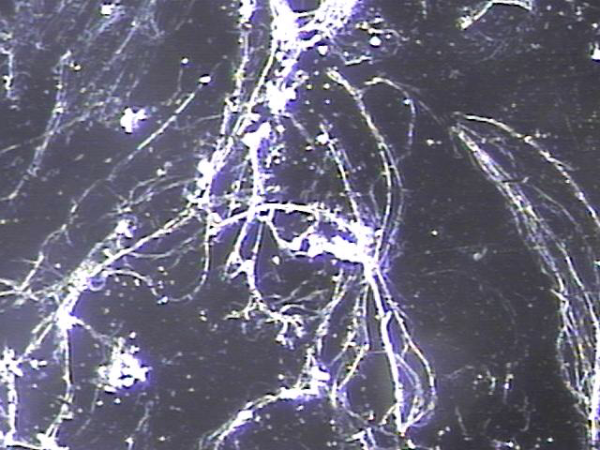

내원 첫날 전립선의 표적 치료후 치료된 정낭의 혈정액과 정자들과 염증들의 현미경학적 자료입니다.

This is a microscopic image taken after your first targeted prostate treatment, showing improvement in the seminal vesicle.

The blood-tinged fluid (hematospermia), sperm, and inflammatory cells have been successfully treated.